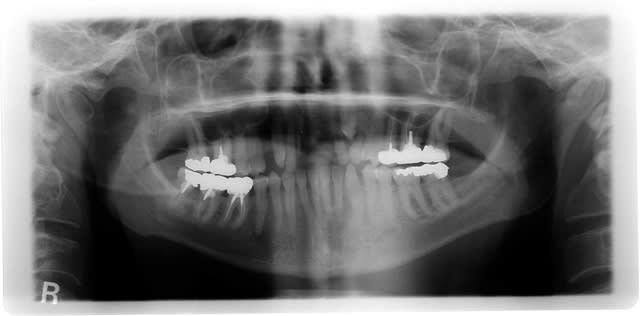

voila tout est dit dans le titre

les radios

63 stable +++

souhait du patient : "avoir deux dents" ignorait que 23 était là je vous mettrai des photos dès que la décision sera prise (...celle du patient) pour la suite après "les deux dents"

Je poserai 2 implants en 11 et en 21 en mentionnant sur le devis que 23 posera un soucis tôt ou tard avec la nécessité de réaliser un traitement de traction orthodontique.

+1 pour 11 et 21 mais ça facile...pour ça rdv déja pris mais regarde mieux 23 tu vois rien d'anormal ?

ortho pour repositionner 13 12 22, corriger la rotation de 14 et voir si la 23 peut être tractée. Puis implant 11 21 et ccm sur 23 si elle est repositionnée sinon extr de 23 et implant aussi pour elle.

pour des raisons esthétiques et mécanique(odf) je préfère mettre en place les deux implants 11 et 21 en premier (en plus il n'était venu que pour ça) puis provisoire sur les deux mise en place systême d'ortho qui nous permettra de gérer

1) l'égression de 12 la rotation de 13 14 en diminuant le diastème

2)ancrage top pour l'ortho

3) alignement des collets facilité

4)réalisation d'une petite provisoire sur 63 en temporisation (extension de 11 et 21) pendant la traction ou avulsion de 22 même si je pense qu'elle est très atteinte

mon seul souci reste la motivation du patient 47 ans maçon pas du tout venu pour ça...;jusqu'ou le compromis doit il aller ?